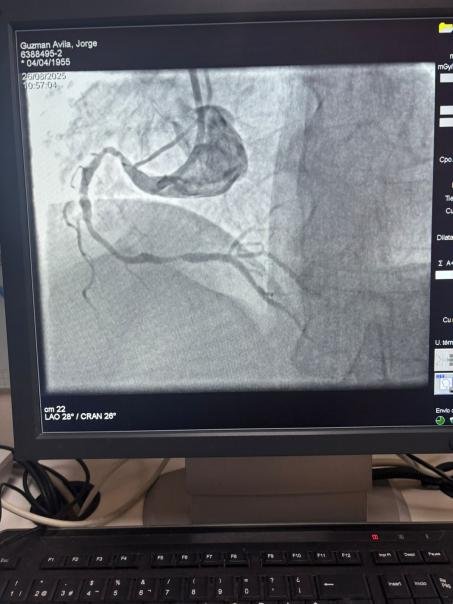

We are proud to share a remarkable case from Hospital Sótero del Río, Chile, where Dr. Martín Valdebenito successfully treated a heavily calcified lesion in the right coronary artery (first curve) using our Vesscrack Coronary IVL Balloon Dilatation Catheter System.

The procedure achieved outstanding results, with the calcified region effectively cracked and vessel flow restored. This marks another milestone in expanding global access to advanced solutions for complex coronary calcification.

The comparison between the pre-procedure and post-procedure angiographic images clearly demonstrates the significant clinical impact of our IVL technology.